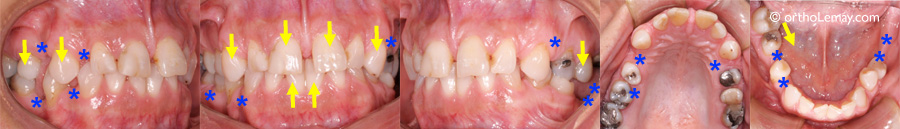

(A) Exemple classique de perte de dimension verticale et d’affaissement postérieur de l’occlusion. Suite à la perte de dents postérieures (indiquées par les *), les dents antérieures se surplombent progressivement et un diastème est apparu entre les incisives supérieures. (A à D) Les flèches indiquent des dents qui migrent suite à la perte des dents postérieures.